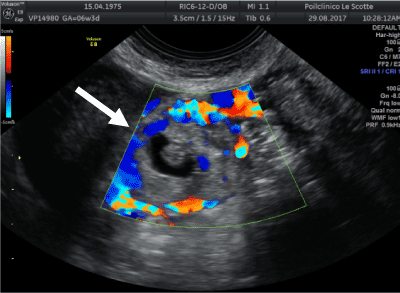

Figure 6. Tubal ectopic pregnancy by transvaginal ultrasound. The arrow indicates the ectopic gestation with circumferential Doppler flow, called the “Ring of Fire”.